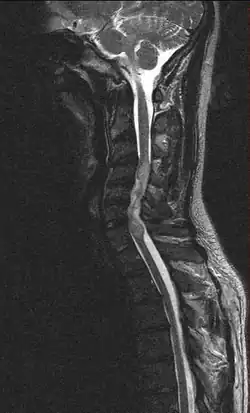

Ependymoma of the cervical spine, completely obscurating the spinal canal |

Froin's syndrome is the coexistence of xanthochromia, high protein level and marked coagulation of cerebrospinal fluid (CSF). It is caused by meningeal irritation (e.g. during spinal meningitis) and CSF flow blockage by tumour mass or abscess.[1] Stagnation of the CSF within the thecal sac facilitates exudation from the tumour itself and activation of coagulation factors. A clinical test formerly used for evaluation of spinal stenosis is Queckenstedt's maneuver. Nowadays, a magnetic resonance imaging is used for identification of CSF flow obstruction. It often shows the prolongation of T1 and T2 signal in CSF caudal to a level of block.[2] This phenomenon is named after Georges Froin (1874–1932), a French physician who first described it.[3][4]